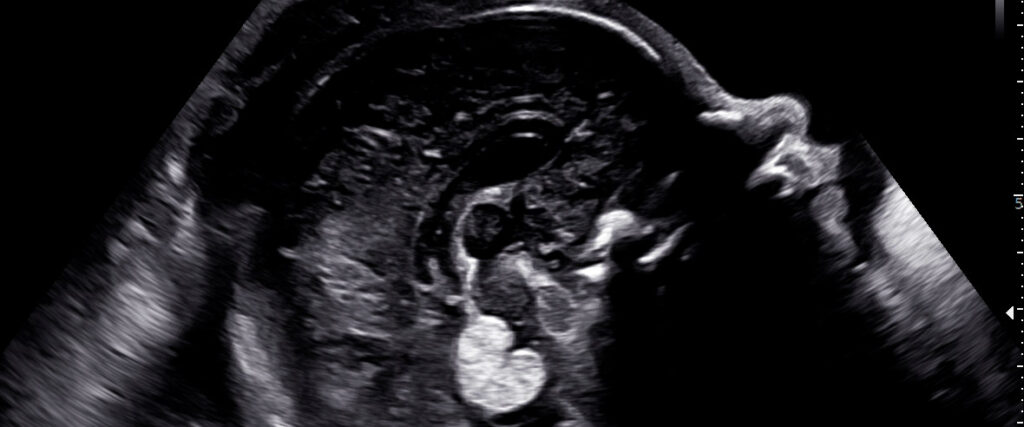

Ultrassonografia detalhada com explicação ponto a ponto durante o exame.

Avaliações completas com tecnologia de ponta e interpretação especializada, garantindo diagnóstico preciso e acompanhamento seguro da gestação.